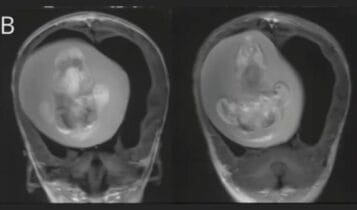

Um feto humano foi localizado às margens da BR-285, em Passo Fundo, na!-->!-->!-->!-->!-->…